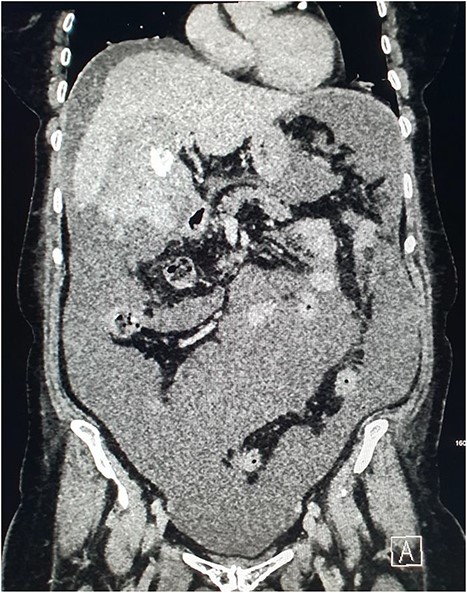

She presented on this occasion with right upper quadrant pain and collapse. Computed tomography (CT) abdomen and pelvis with intravenous contrast in the portal venous phase was performed, demonstrating perforated acute calculous cholecystitis and active haemorrhage (Fig. 1). At this point, Interventional Radiology and Upper gastrointestinal (GI) Surgery in our institution were contacted, and the patient was transferred for emergency embolization. The patient was haemodynamically unstable, so the massive transfusion protocol was commenced.

CT abdomen and pelvis with intravenous contrast in the portal venous phase was performed demonstrating perforated acute calculous cholecystitis and active haemorrhage.